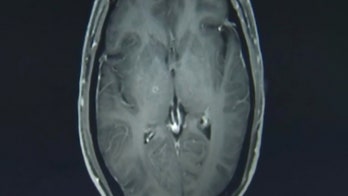

Foodborne Illness November 25, 2019 Man had hundreds of tapeworms in brain, chest after eating undercooked pork Jianrong said his patient is doing well after one week, but the long-term effects from the massive infestation are unclear.